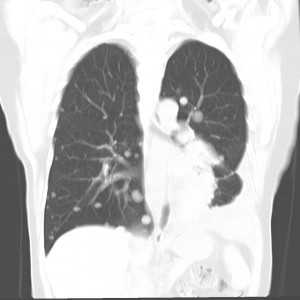

Множественные гематогенные вторичные узлы при раке почки, компьютерная томография (КТ).